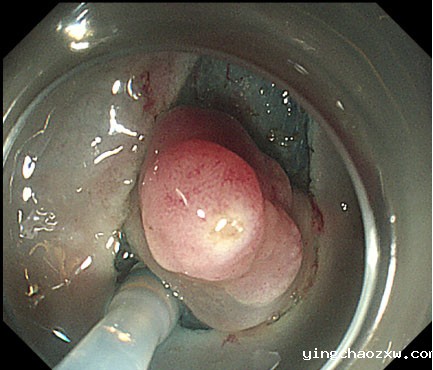

平滑肌瘤内镜下剥离术

内镜下剥离术